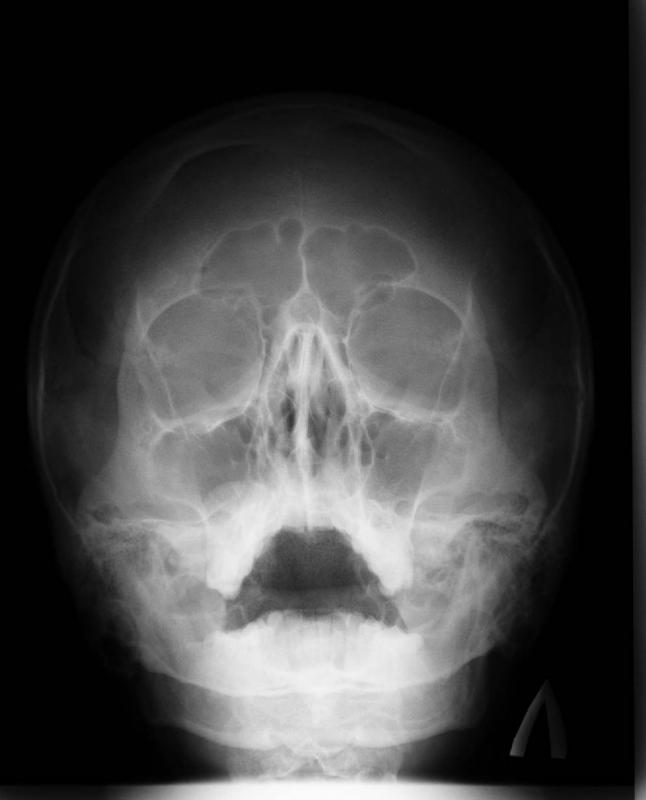

На представленій рентгенограмі придаткових пазух носа візуалізується зниження пневматизацію лівої верхньощелепної пазухи в нижній третині з верхнім горизонтальним рівнем. Висновок: рентген-ознаки лівостороннього верхньощелепного синуситу (гаймориту).

На знімку вище можна простежити пристінкове затемнення обох гайморових пазух. Опис приведе до логічного висновку про двосторонньому гаймориті.

Рентген пазух носа здорової людини виглядає так:

- Носова перегородка поділяє носову порожнину на симетричні сторони трикутника.

- Білі смуги, що проходять праворуч і ліворуч розділеної області — це носові ходи.

- Трикутні порожнини з боків носа — гайморові пазухи.

- Між ямками розташована решітчаста пазуха з тонкими стінками, осередки якої повинні добре проглядатися.

- Вище очниць визначаються лобові пазухи, які можуть мати різну форму. Допускається їх поділ кістковими перегородками.

- У пазухах повинен знаходитися повітря. Їх краю, як і контури кісток, повинні бути чіткими і рівними.

Про діагностування патології можна говорити, якщо знімки показують наступне:

- затемнення ділянки;

- потовщення;

- наявність порожнини різної форми;

- деформація кісткової тканини.

Для гострого запалення характерні потовщення слизової і деформація її кордонів (при гнійному вмісті). Наявність і рівень рідини встановлюються по горизонтальному розмежування в пазухах. Про склад вмісту рентген не розповість, для цього знадобиться зробити пункцію (прокол).